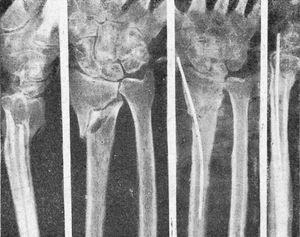

Figura 1. Fractura tercio superior fémur transversal, reciente, enclavijamiento cerrado. La misma, una vez enclavijada; correcta reducción e inmovilización que permiten la marcha sin ningún otro procedimiento secundario de inmovilización.

Figura 2. Fractura transversal tercio medio tibia, sin desviación, peroné íntegro, enclavijamiento cerrado; fue uno de los primeros casos tratados, y a los tres meses reanudaba el trabajo; un solo clavo mantuvo una perfecta inmovilización.

Figura 3. Fractura tercio medio tibia y peroné; enclavijamiento cerrado con un solo clavo; un tercer fragmento impide la exacta coaptación de fragmentos, obteniéndose, no obstante, una buena consolidación con predominio de callo periostal; se aprecia en la parte superior el orificio de la trepanación de entrada del clavo.

Figura 4. Enclavijamiento mixto en una pseudoartrosis de cúbito y radio, previo refrescamiento de fragmento. Fue utilizado alambre en cúbito por no disponer entonces de tallo suficientemente largo. La misma, una vez obtenida la consolidación.